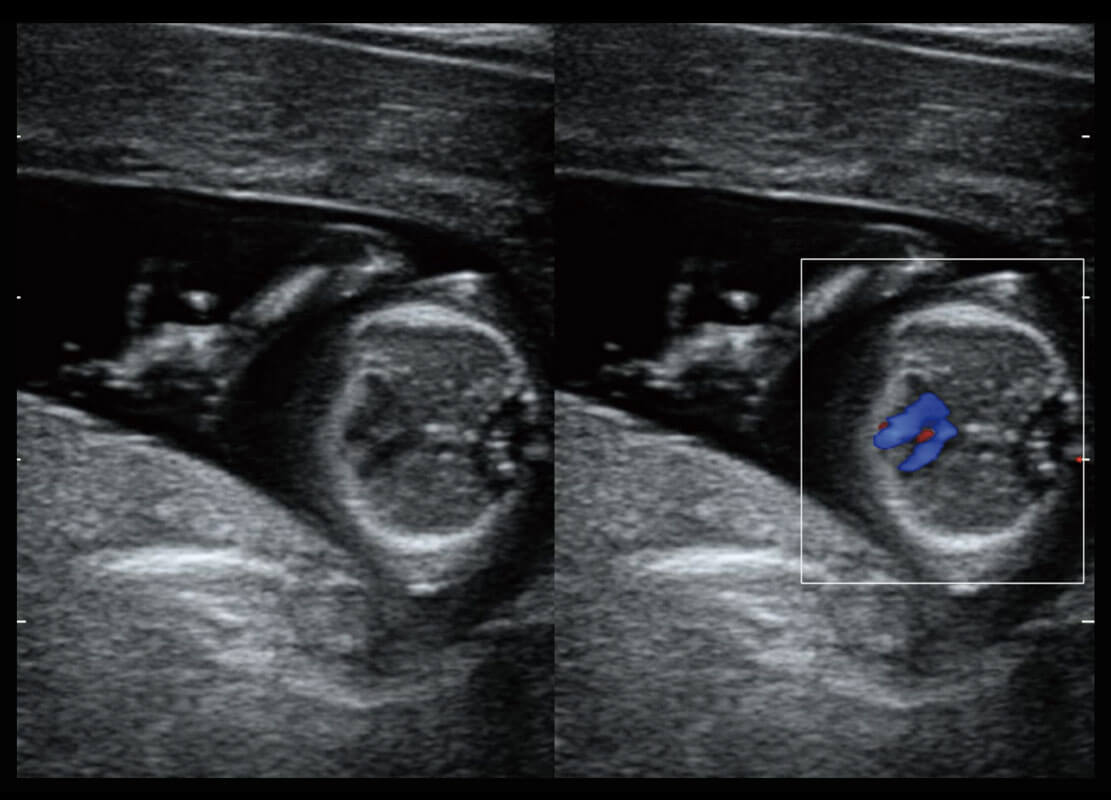

P60搭载一系列胎儿心脏成像技术,实现精细的胎儿心脏评估。

胎心容积成像